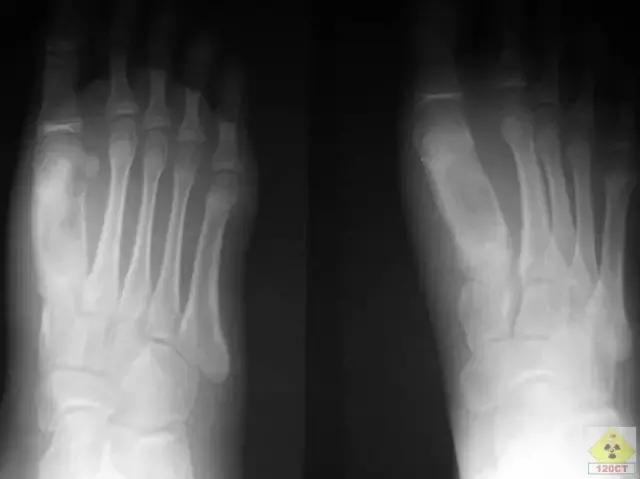

一般的骨、关节结核的好发部位首先为脊椎,其次为髋关节及膝关节、短骨及长骨骨干。外伤可使隐性骨结核病灶变成活动性骨结核。负重大或运动多的肢体或关节发生率较高,以负荷最重的胸腰段最易发生结核病。下肢结核比上肢结核多见。